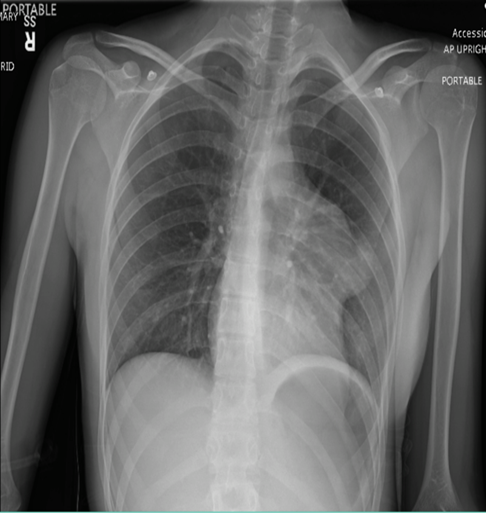

Figure 1: Chest X-ray. Left mediastinal 6.1 cm lobulated opacity, possibly a pericardial cyst or other mass.